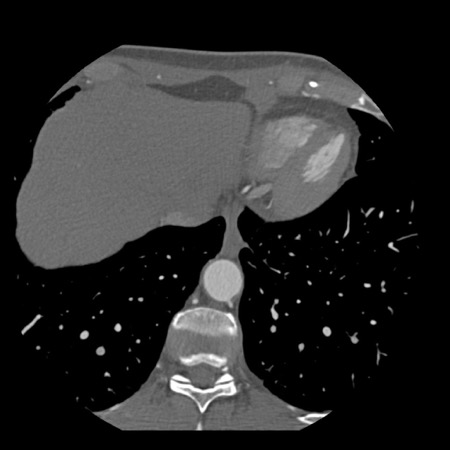

case 4 – CAD-RADS 3/P1/I+ thrombus left ventricle

First, scroll through the CTA images.

How would you describe the findings on the coronary CTA?

The findings are:

- Moderate (50-69%)

stenosis in the proximal LAD caused by a non-calcified plaque. - Variant of

sinoatrial (SA) nodal artery. The artery usually arises from the RCA as a second

branch after the conus artery, however in this case it arises from the LCX,

courses behind the aorta, anastomosing with the right atrium and with a small

branch supplies the SA-node of the heart. - Thrombus in the

apex of the left ventricle. - CTP was performed

in this patient. CTP showed a perfusion defect at stress imaging in the

territory of the LAD (I+), at rest no perfusion defect was visible.

This patient classifies as CAD-RADS 3/P1/I+, which means

this patient requires further investigation.